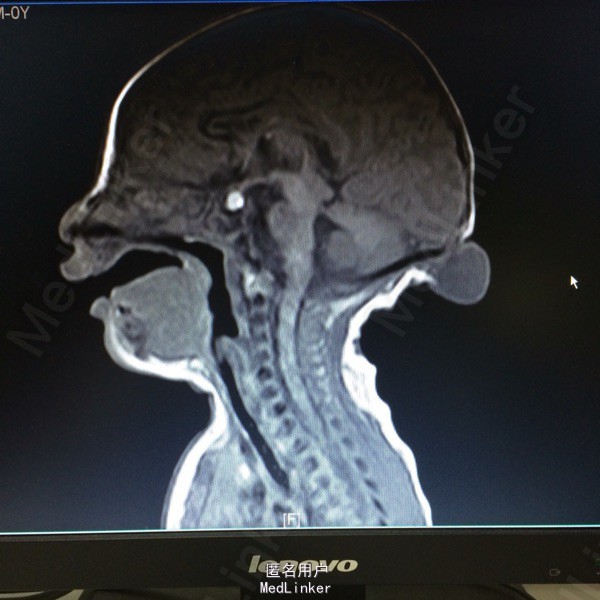

主诉:发现枕部包块1月余 病史:患儿2月大,第3胎第3产,经剖宫产,查体发现枕后部有一圆形肿物突出,约等3*3大小,透光实验阳性,质软。

查体:神志清醒,枕后部可见一圆形肿物突出,约3*3cm大小。质软,表面无溃疡等 辅助检查:胸片提示新生儿羊水吸入综合症,头颅MR提示局部脑脊膜膨出

诊断:后枕部脑脊膜膨出 处理:行脑脊膜膨出修补术,病理提示符合脑脊膜膨出